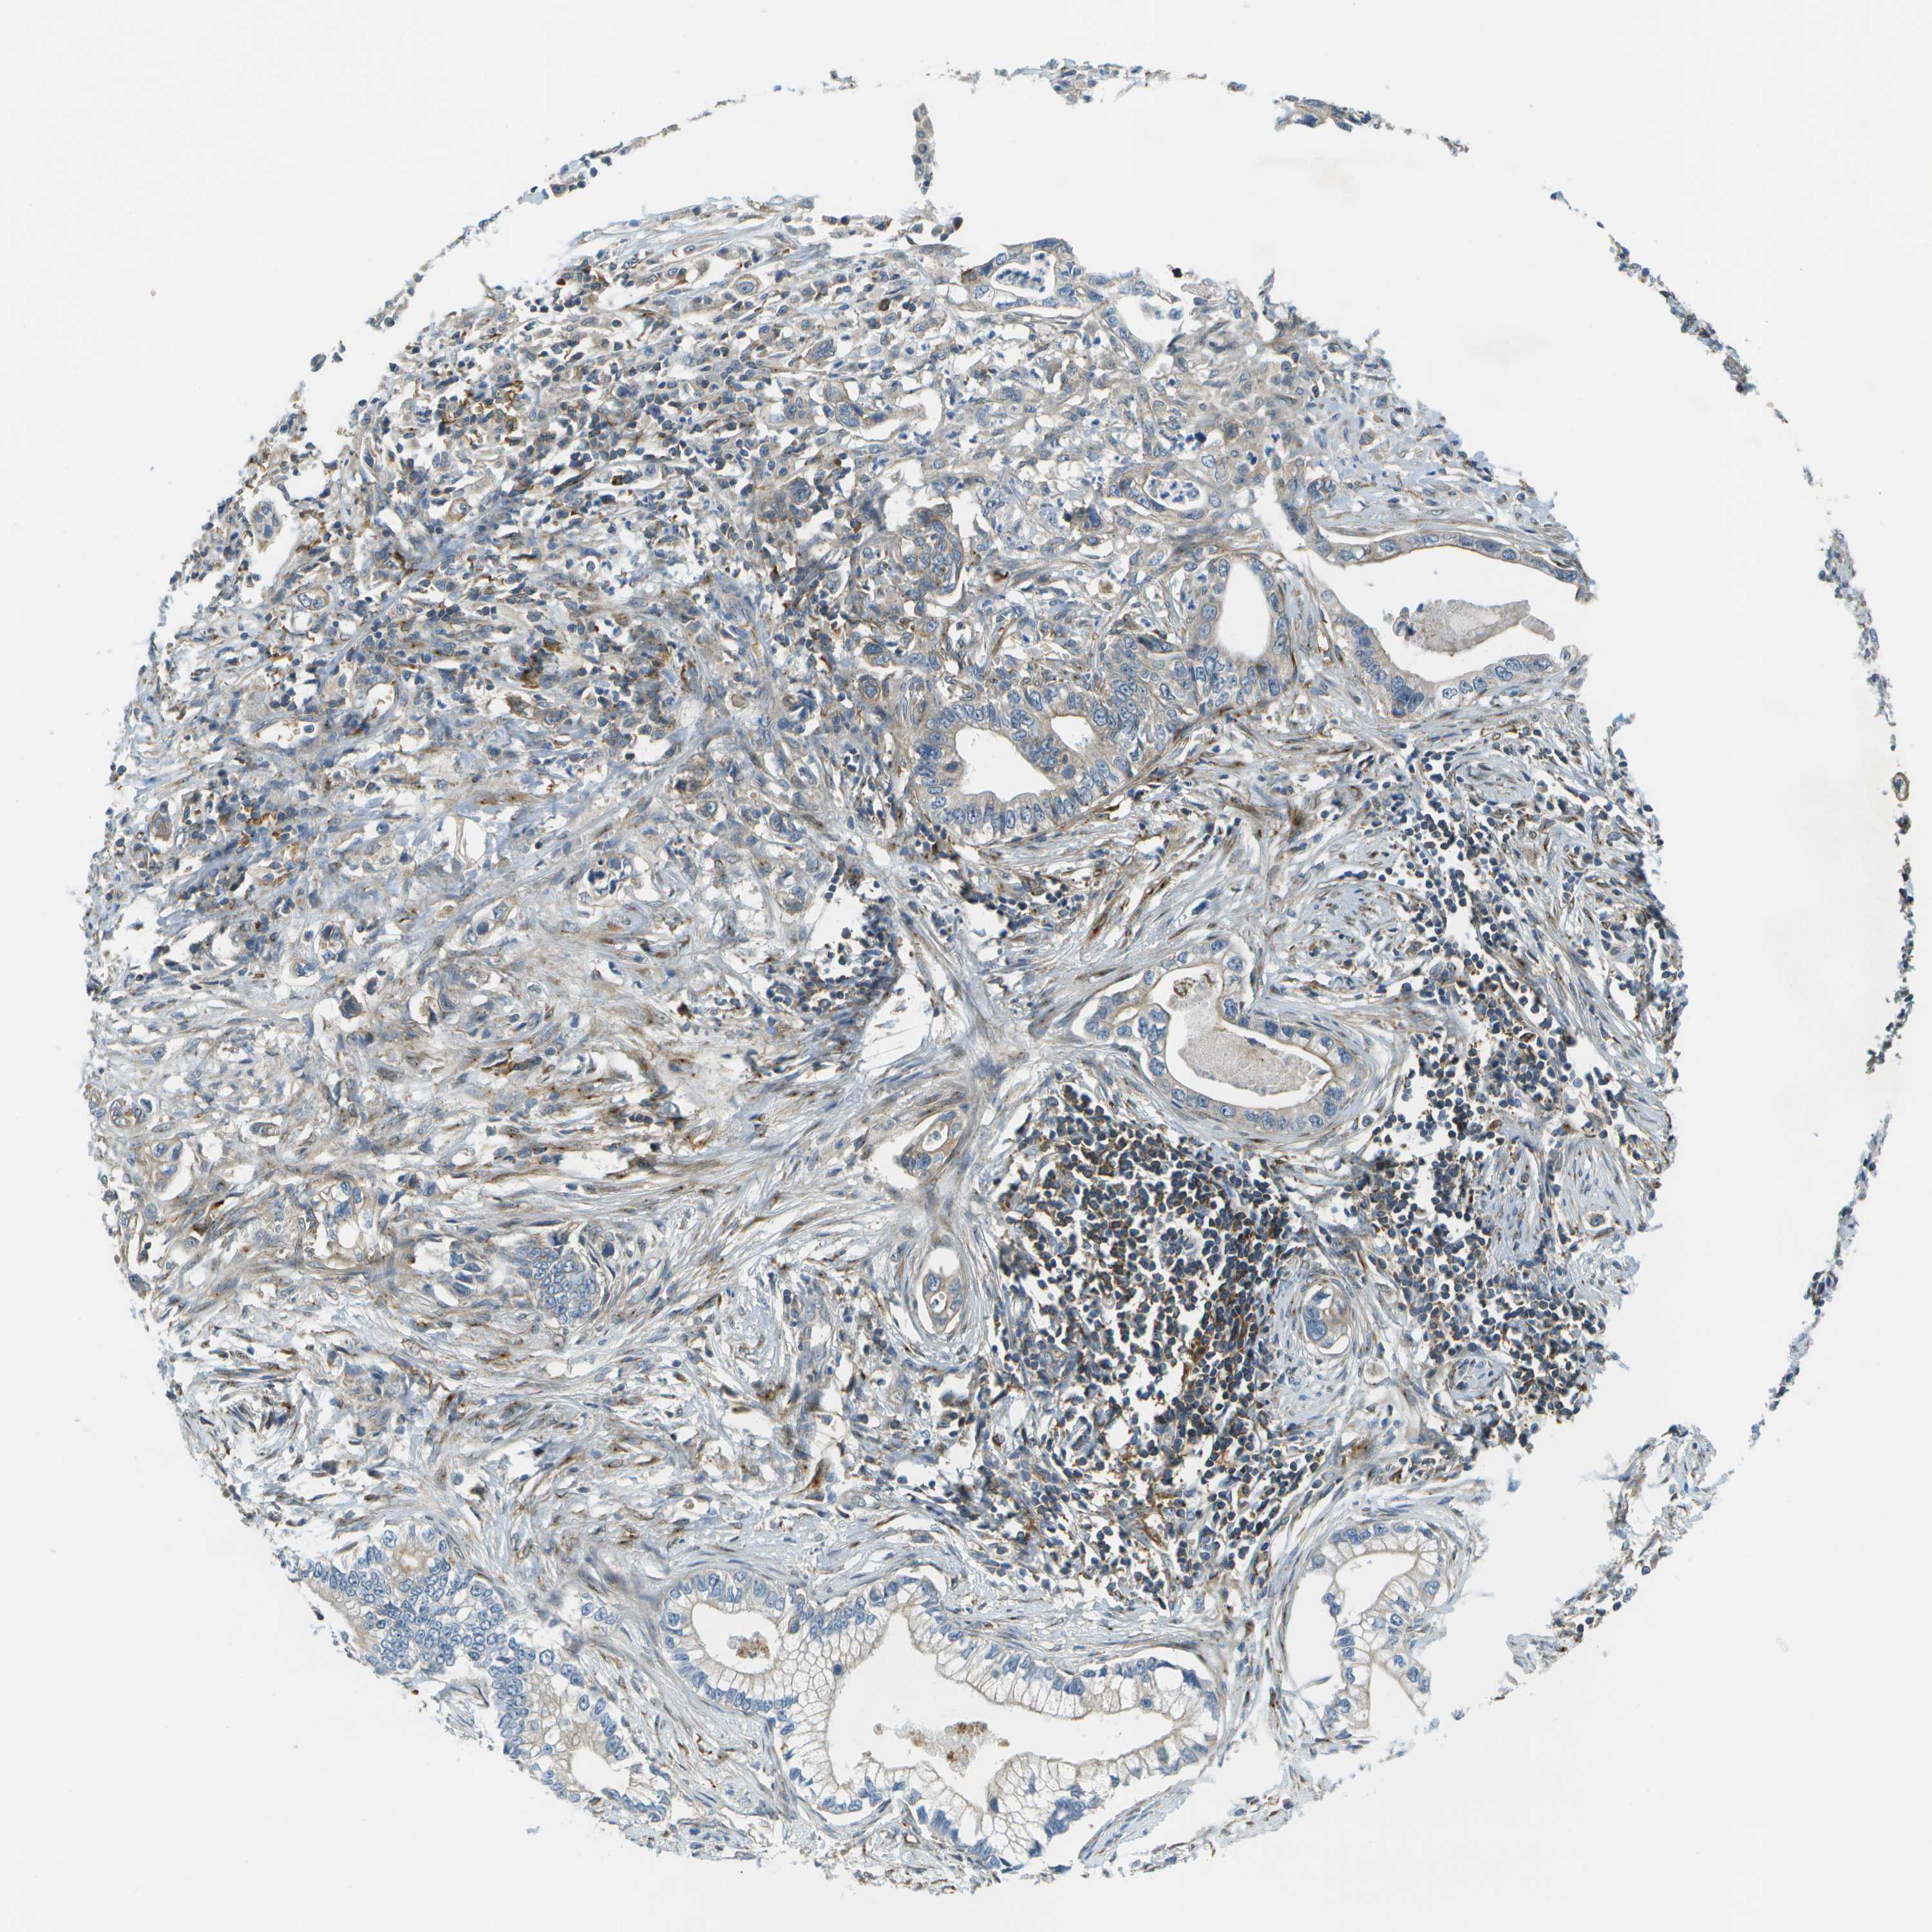

PANCREATIC CANCER - Protein expressioni

A mouse-over function shows sample information and annotation data. Click on an image to view it in a full screen mode. Samples can be filtered based on level of antibody staining by selecting one or several of the following categories: high, medium, low and not detected. The assay and annotation is described here.

Note that samples used for immunohistochemistry by the Human Protein Atlas do not correspond to samples in the TCGA dataset.

Antibody stainingi

Antibody staining in the annotated cell types in the current human tissue is reported as not detected, low, medium, or high, based on conventional immunohistochemistry profiling in selected tissues. This score is based on the combination of the staining intensity and fraction of stained cells.

Each image is clickable and will lead to virtual microscopy that enables deeper exploration of all samples and also displays staining intensity scores, fraction scores and subcellular localization as well as patient and tissue information for each sample.

Antibody HPA016865

Antibody HPA024801

Staining

High

Medium

Low

Not detected

Intensity

Strong

Moderate

Weak

Negative

Quantity

>75%

75%-25%

<25%

None

Location

Nuclear

Cytoplasmic/membranous

Cytoplasmic/membranous,nuclear

Adenocarcinoma, NOS